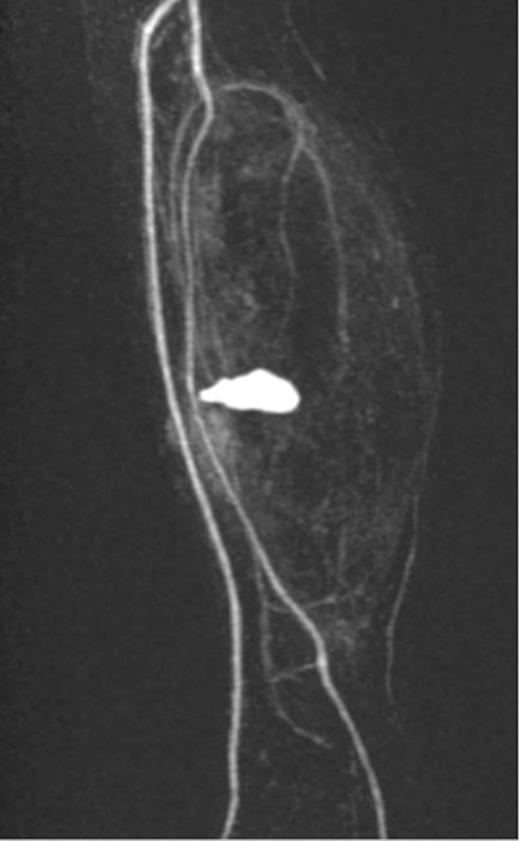

A 20-year-old man with no past medical history presented to the emergency department with non-displaced and closed transverse fracture of the left mid-tibial shaft and an intact fibula induced by a tackle during a football match. On examination, he had no neurovascular deficit and all crural pulses were palpable. His fracture was treated conservatively with a non-weight bearing above knee plaster cast later replaced by a below knee cast for a total period of 6 months. Upon examination during his attendance to the facture clinic, x-ray demonstrated no signs of fracture union. The subsequent magnetic resonance imagining (MRI) confirmed a nonunion of the fracture along with an ovoid 2.7 cm posterior compartment vascularized mass causing bowing of the interosseous septum with no evidence of avascularity of the bony margins (Fig. 1). This was confirmed to be a pseudoaneurysm originating from the PTA. An endovascular approach was adopted, and the pseudoaneurysm was injected with 2 ml of thrombin, filled with multiple coils and deployment of an angiography balloon (in the sac) (4 mm × 6 cm) for 7 min (Fig. 2). This resulted in complete cessation of the pseudoaneurysm with normal flow in the PTA (Fig. 3). The residual extravasated hematoma was later drained by an open approach. Follow-up x-ray (6 months) demonstrated complete union of the fracture site with no associated complications.

Angiographic image, demonstrating the site of the nonunion, coil insertion to the pseudoaneurysm and extravasated contrast.